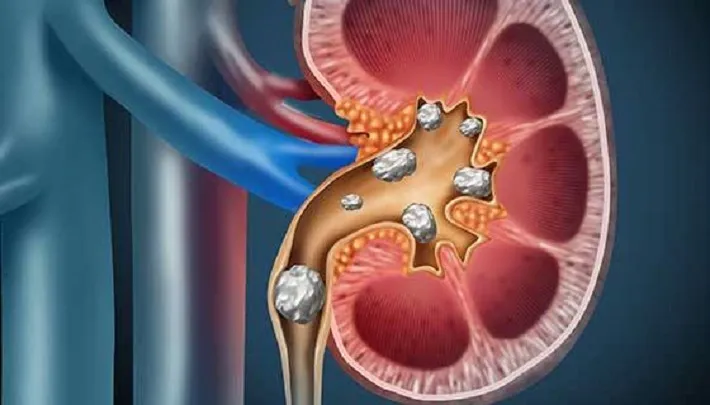

झापा, ११ भदौ । झापाका एक बिरामीको उपचारको क्रममा पित्तथैली र मूत्रनलीबाट शल्यक्रियामार्फत ५५ वटा पत्थरी निकालिएको छ । दक्षिण झापाको कचनकबल गाउँपालिका वडा नं ६ की ५४ वर्षीया सुमित्रा साहको भद्रपुरस्थित ओमसाई पाथिभरा हस्पिटलमा उपचारको क्रममा ५५ वटा पत्थरी एकैपटकमा बाहिर निकालिएको हो ।

“सहन नसक्ने गरी पेटभित्र दुखाइ भएको भन्दै उनलाई अस्पतालमा भर्ना गरिएको थियो”, निर्देशक पोखरेलले उपचारबारे जानकारी दिँदै भने, “मेडिकल सुपरिन्टेन्डेन्टसमेत रहनुभएको सर्जन डा. शशी सिंहले उनको स्वास्थ्य परीक्षणपश्चात तुरुन्त शल्यक्रिया गरिएको थियो ।” सबै जाँच प्रक्रिया पूरा भएपछि शल्यक्रिया गर्दा पित्त थैली र मूत्रनलीबाट ५५ वटा पत्थरी निकालिएको उनको भनाइ छ ।

एउटै व्यक्तिको पित्तथैलीमा यतिका धेरै पत्थरी भेटिनु दुर्लभ नै भएको चिकित्सक बताउँछन् । “एउटै स्टोन हुँदा दुखेर बिरामी निकै पीडामा छटपटाउँछन्,” साहलाई अस्पतालको सर्जिकल वार्डमै भेटेर स्वास्थ्यलाभको कामना गरेको हल्दिबारी गाउँपालिकाका अध्यक्ष रवीन्द्र लिङ्देनले भने, “यति धेरै स्टोन बोकेर कसरी सहेर बस्नु भएको थियो होला भनेर म चकित भएको छु ।”

अस्पतालका व्यवस्थापक मनोज दाहालले उनको पित्तथैली र मूत्रनलीबाट निकालिएका हरेक पत्थरी १२ एमएमभन्दा ठूलो रहेको जानकारी दिए । रासस